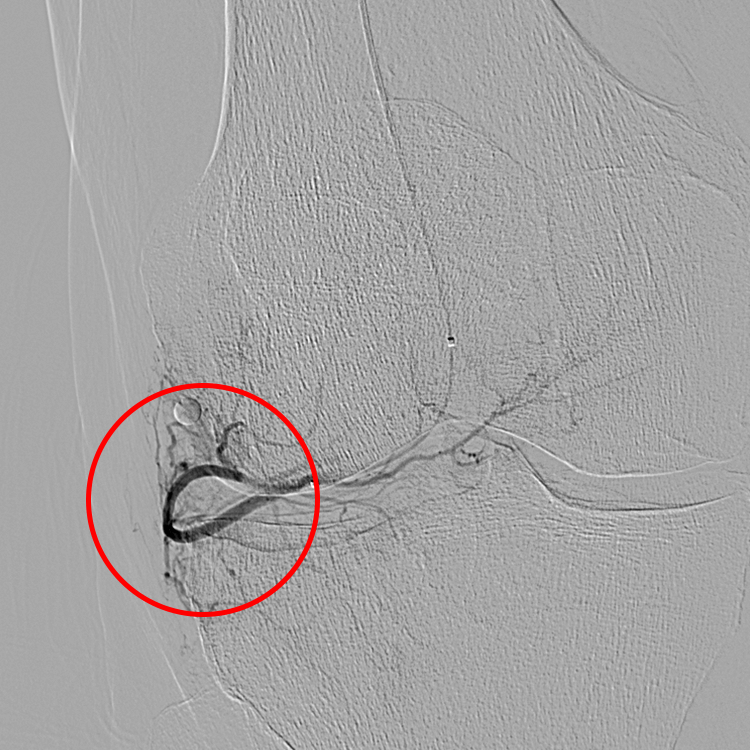

GAE Before and After Pictures

Before treatment, there are enlarged small arteries to the inflamed lining of the knee (synovium) (red circle).